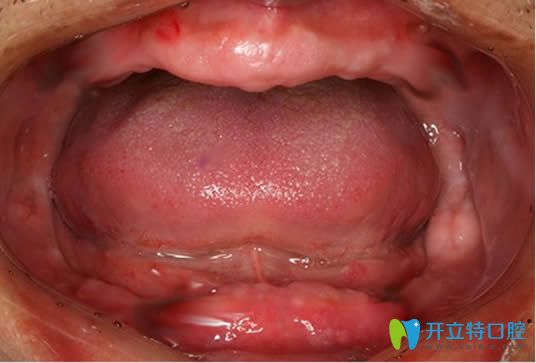

全口吸附性義齒主要是根據(jù)個(gè)人牙槽骨條件,由醫(yī)生精細(xì)取模和后期技師的制作,才能使義齒達(dá)到充分的邊緣封閉,和牙床產(chǎn)生牢固的吸附力,下文就有講解,并附bps生物吸附性義齒的收費(fèi)價(jià)格

吸附性義齒是目前適用比較廣泛的全口假牙制作系統(tǒng),簡(jiǎn)稱(chēng)BPS。下面就看牙科醫(yī)生全面揭秘什么是全口吸附性義齒及吸附性義齒的優(yōu)缺點(diǎn)。